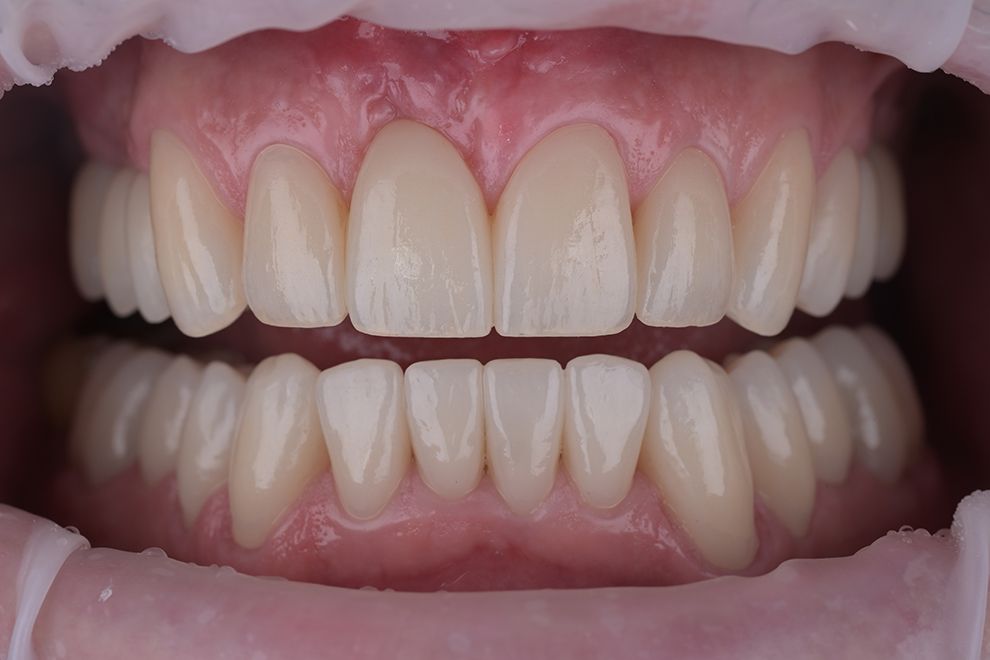

до и после